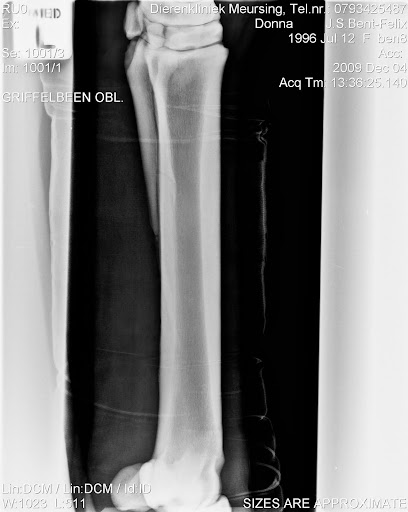

Me meisje is eindelijk weer thuis, na een geslaagde operatie.

De wond ziet er erg netjes uit, na een week mag het verband eraf en dat wordt vervangen voor stalbandages en dan mogen we beginnen met stappen aan de hand, langzaam aan, een maandje rustig aan doen en dan mogen we langzaam aan weer beginnen met opbouwen.